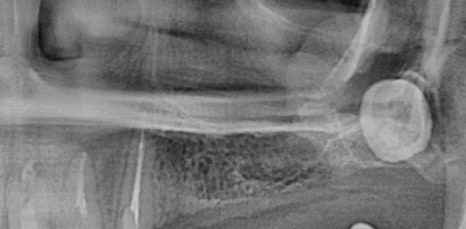

특히 위쪽 어금니 쪽이 상실 되어 임플란트 시술을 진행해야 하는데 잇몸 뼈가 부족한 상태라면 추가적으로 상악동거상술을 함께 진행해야 했어요. 상악동이란 코 양옆에 위치하고 있으며 뼈 속에 비어 있는 공기 주머니로 두개골의 무게를 줄여주는 곳이었어요. 상악동은 아주 얇은 막으로 둘러 쌓여 있으며 상악 쪽의 잇몸 뼈가 부족한 상태로 임플란트를 식립 하게 된다면 상악동 막이 찢어지거나 천공이 생길 수 있었어요.

상악동에 천공이 생기게 된다면 염증으로 인해 부작용이 생길 수 있었어요. 그렇기 때문에 환자 개개인마다 크기와 위치가 모두 다른 상악동의 위치와 잇몸 뼈의 두께를 정확히 파악하는 것이 중요했어요. 정밀 검사 후 임플란트를 식립 하기에 잇몸 뼈의 양이 부족하다는 진단이 나오게 된다면 얇은 상악동 막을 들어올려 준 후 필요한만큼의 뼈 이식을 진행해 주는 방법이 상악동거상술이었어요.

신논현역임플란트에서 말하는 상악동거상술은 치조정접근법과 측방접근법인 두가지 방법으로 진행할 수 있었어요. 남아 있는 잇몸 뼈의 양에 따라 이식 해야 하는 양이 달라지고 그로 인해 상악동에 접근 하는 방법을 기준으로 두가지 방법은 나눠 지고 있었어요. 먼저 치조정접근법은 잇몸 뼈가 4-8mm 정도 확보 되었을 때 사용하는 방법으로 치아가 상실 된 위치의 잇몸에 작은 구멍을 뚫어 준 뒤 그 구멍을 통해 상악동 막을 들어 올린 후 뼈 이식을 진행하는 방법이었어요.

작은 절개 범위와 뼈 이식 양이 많지 않기 때문에 수술 시간이 짧고 통증과 붓기도 적으며 회복 속도 또한 측방접근법에 비해 빠른 편이었어요. 반면 측방접근법은 잇몸 뼈가 4mm 이하로 많은 양의 잇몸 뼈를 이식 해야 할 때 필요한 방법이었어요. 잇몸 측면에서 큰 창 모양으로 절개 후 접근하는 방법으로 수술시간이 길고 붓기, 통증이 큰 편으로 회복 속도 또한 더딘 편이었어요.

하지만 시야 확보가 잘 되어 출혈과 돌발 상황에 대한 대처를 빨리 할 수 있어 안전하게 수술을 마무리 할 수 있다는 장점이 있었어요. 치조정접근법과 측방접근법 두가지 방법 중 어떠한 방법이 더 유리하고 안전하다고 할 수 없으며 치조골의 상태와 식립 해야 하는 임플란트의 개수, 상악동의 위치와 두께 등을 고려하여 환자분께 적합한 방법으로 상악동거상술을 진행 하는 것이 가장 안전하고 좋은 방법이라고 할 수 있었어요.